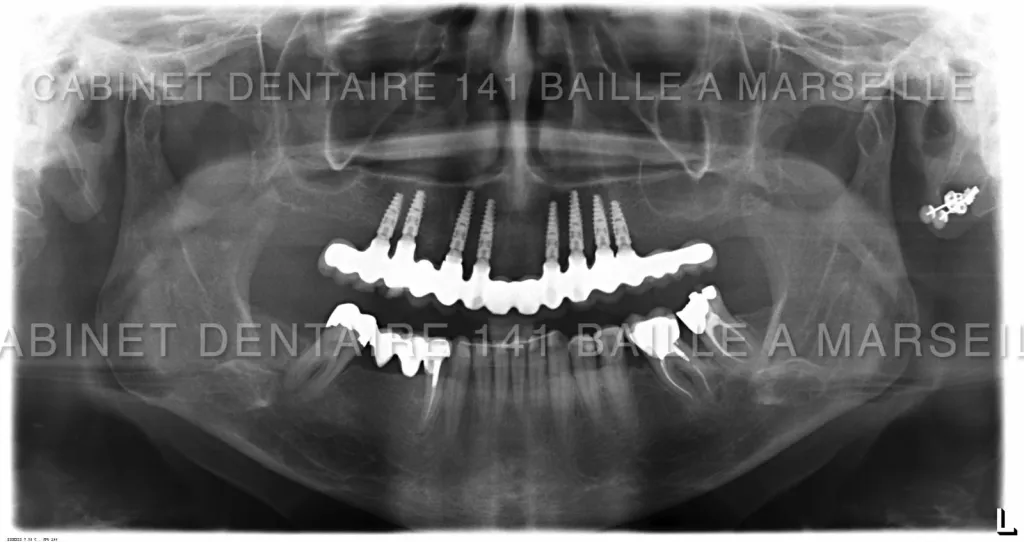

changer toutes ses dents par des implants marseille Cabinet dentaire 141 baille

Remplacer toutes ses dents par des implants à marseille

Dans certains cas il n'y a pas d'autres solutions que le remplacment de toutes les dents par des implants .Dernières techniques d'implantation Totale en MCI.

Cabinet denatire du docteur didier Tourrolier 13005 marseille

Notre protocole opératoire chirurgical lors des implantations totales

FICHE PROTOCOLE CHIURGICAL DE NOS IMPLANTATIONS TOTALES EN MCI: FICHE ESPACE PROFESSIONNEL CONFRERES: